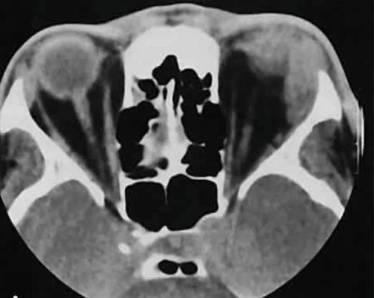

- КТ или рентген позвоночника;

- МРТ позвоночного столба или внутренних органов;

- УЗИ брюшной полости.

По снимкам можно определить, почему болит низ или верх спины слева. От заключения зависит дальнейшее лечение. Иногда обследование дополняется анализом крови и мочи.

Методы диагностики, при помощи которых врач может выяснить истинную причину подобных болей в спине:

- Компьютерная томография (сокр. КТ);

- Ультразвуковое исследование (УЗИ) внутренних органов;

- Магнитно-резонансная терапия (сокр. МРТ);

- Общий и биохимический анализ крови и мочи.